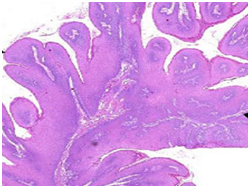

Histopathological statutes: The squamous epithelium displays finger like projections, the epithelial maturation pattern is orderly with epithelial hyperkeratosis. Spinous epithelial cells may depict cytoplasmic vacuolation with pale, clear perinuclear haloes, nuclear pyknosis and infrequent basilar hyperplasia. Oral squamous papillomas frequently display koilocytosis on account of the co-existent cytopathic influence. Atypical nuclear alterations may be exemplified; particularly with immune-compromised (HIV positive) individuals.9 The epithelium displays a typical maturation pattern with prominent hyperkeratosis. Epithelial to basal cell quantification is moderate (basilar hyperplasia) along with an extensive koilocytic transition.1 Virally induced carcinomas are the poorly differentiated, non-keratinizing tumours and may be enunciated in the tonsils of sexually active young men. Majority of the tumours elucidate the p16 proteins. Oro-pharyngeal cancers which are reactive for human papilloma virus (HPV) frequently depict basaloid morphology. Apart from a viral genesis, squamous papillomas may ensue from mechanical irritation or may be genetically determined as a constituent of Cowden’s syndrome.

Figure 3 Papillomas with a fibro-vascular core.

Figure 4 Papillomatous lesions with a prominent fibro-vascular core.